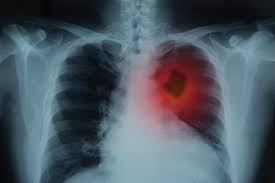

Can You Detect Lung Cancer With Ct Scan : Lung Cancer Snmmi : It can also look at your liver and adrenal glands.. The ct scan might show signs of cancer, but that cancer might not be active for example, it could be scar tissue left over from cancer killed off by your treatment this means you won't know whether or not you need to continue treatment Lung cancer typically goes undetected until it reaches stage 3 or 4. If you are a smoker, it is highly recommended to have a ct scan every 3 months. It can also show whether the cancer has spread outside the lung. But the test is not helpful for light smokers or people who quit smoking more than 15 years ago.

This is because there are very few symptoms related to the condition until it gets to an advanced level. After cancer treatment, a ct scan is unable to determine whether masses leftover are cancerous: Alternatively, you should take lung ct scans if you are concerned or if you show any symptoms. Sometimes iv contrast is administered while the images are being obtained, as this can help radiologists define certain structures and pathology. A computer then combines these images into a detailed picture of your lungs. Doctors can use a ct scan to look for lung cancer. Need help kicking the tobacco habit? While it might seem obvious to assume that finding small tumors reduces one's likelihood of dying from lung cancer , this is incorrect.

One of our lung nurse navigators will answer your questions, assist you with a referral to a primary care physician, and help you schedule your screening. People who already have symptoms that might be caused by lung cancer may need tests such as ct scans to find the underlying cause, which in some cases may be cancer. 95% of nodules found are benign. While not all detected lung nodules should be reported, radiologists. A computer then combines these images into a detailed picture of your lungs. But this kind of testing is for diagnosis and is not the same as screening. Doctors can use a ct scan to look for lung cancer. When you get a ct scan, you lie on a table while a machine rotates around your. A lung scan using either a ct scan or an ultrasound can detect these early signs of cancer. If you are a smoker, it is highly recommended to have a ct scan every 3 months. Computed tomography (ct) scans detect tumors, but do not determine whether they are malignant or not. This is because there are very few symptoms related to the condition until it gets to an advanced level. While it might seem obvious to assume that finding small tumors reduces one's likelihood of dying from lung cancer , this is incorrect.

People who already have symptoms that might be caused by lung cancer may need tests such as ct scans to find the underlying cause, which in some cases may be cancer. When you get a ct scan, you lie on a table while a machine rotates around your. Sometimes iv contrast is administered while the images are being obtained, as this can help radiologists define certain structures and pathology. Thanks to advances in medical technology, a computed tomography (ct) scan now allows doctors to detect lung cancer even during its early stages. If you are a smoker, it is highly recommended to have a ct scan every 3 months. It can also look at your liver and adrenal glands. Lung cancer typically goes undetected until it reaches stage 3 or 4. Because the risk of developing lung cancer is much greater than the added risk from a ct scan, and smoking increases the risk of lung cancer, we feel the benefits of ct screening for lung cancer in patients with a significant history of. The risk of developing lung cancer due to a single ct scan of the chest is estimated to be one in 10,000. Patients known to have lung cancer at the time of cardiac ct were excluded. The scan looks at your lungs and other parts of your chest. Most doctors do not recommend pet/ct scans for routine follow up of patients after lung cancer treatment. This can include a chest computed tomography (ct) scan and, if a nodule or mass is found, a biopsy.